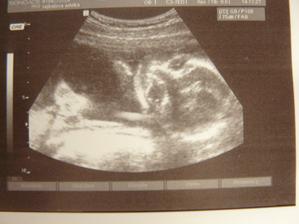

Milované miminko na cestě ♥

Prožívám to nejšťastnější a nejkrásnější období v životě ženy a to díky tomu, že čekáme naše milované miminko!!! ♥ Největší zásluhu má na tom můj manžel, který mi slpnil to, po čem jsem kdy toužila, a bez kterého bych nikdy to, co prožívám, neprožívala. V srpnu 2009 jsme se z velké lásky k sobě vzali a v srpnu 2010 se z naší velké lásky narodí miminko jménem Leošek ♥